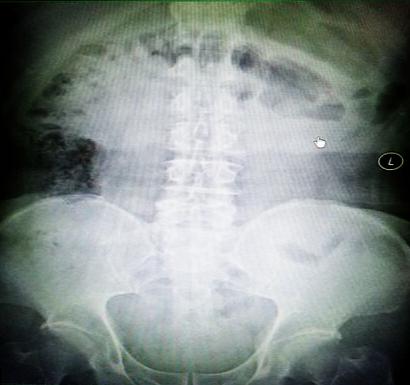

受試患者在結(jié)腸端端吻合術(shù)中,使用我司新研制產(chǎn)品達(dá)到了理想的預(yù)期效果。患者術(shù)后7天、14天X光片顯影,可降解腸道支架均能按研制設(shè)計(jì)的預(yù)期時(shí)間節(jié)點(diǎn)保持應(yīng)有強(qiáng)度,術(shù)后21天X光片顯示可降解腸道支架已完全破碎,并排出體外。在整個(gè)試驗(yàn)過(guò)程中,病患無(wú)任何不良反映,耐受良好。